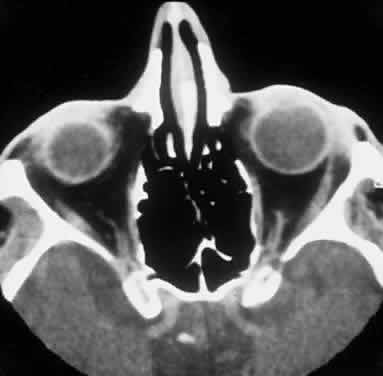

Computed tomography (CT) accurately demonstrates the molding of the mass to orbital structures, such as the globe and orbital bones, without bony erosion except in large cell lymphoma (Fig. 7). CT is used to localize the lesion, which tends to be unilateral and in both the intraconal and extraconal spaces. Lesions limited to the conjunctiva tend to be more benign with a better long-term prognosis, whereas those that extend into the orbit tend to be more malignant. Conjunctival lesions remain localized in 90% of cases, whereas orbital and lid lesions have a higher rate of systemic extranodal involvement.63 Lymphoid lesions of the lacrimal gland appear as a diffuse vertical expansion of the gland, which mold to both the globe and orbital bone without producing a bony fossa or erosion64 (Fig. 8). If the lesion extends beyond the orbital rim, the palpebral lobe of the gland is involved, and posterior or orbital lobe involvement appears as a straight line against orbital fat. Pleomorphic adenoma, on the other hand, appears as an oval, globular lesion with, in 80% of cases, adjacent bone changes caused by the firmer stroma of the tumor. Because epithelial tumors usually arise in the orbital lobe, extension beyond the orbital rim is not a feature.65 CT scan cannot distinguish between inflammatory and lymphoid lesions, because both lesions are homogeneous and enhance with intravenous contrast, and at biopsy, orbital lymphoid lesions are pink with a friable texture caused by the absence of stroma.66–68 The subtype and malignancy of the lesion can only be determined morphologically. The following subtypes of B-cell nonHodgkin's malignant lymphoma—extranodal B-cell marginal zone lymphoma, follicle center cell lymphoma, small lymphocytic lymphoma, lymphoplasmacytoid lymphoma, mantle cell lymphoma, large cell lymphoma, and Burkitt's lymphoma—are discussed in the approximate order of frequency with which they occur in the orbit.

Fig. 8. A CT scan, axial view, of a B-cell lymphoma localized to the anterior orbit bilaterally, with left lacrimal gland involvement and a normal adjacent lateral wall.